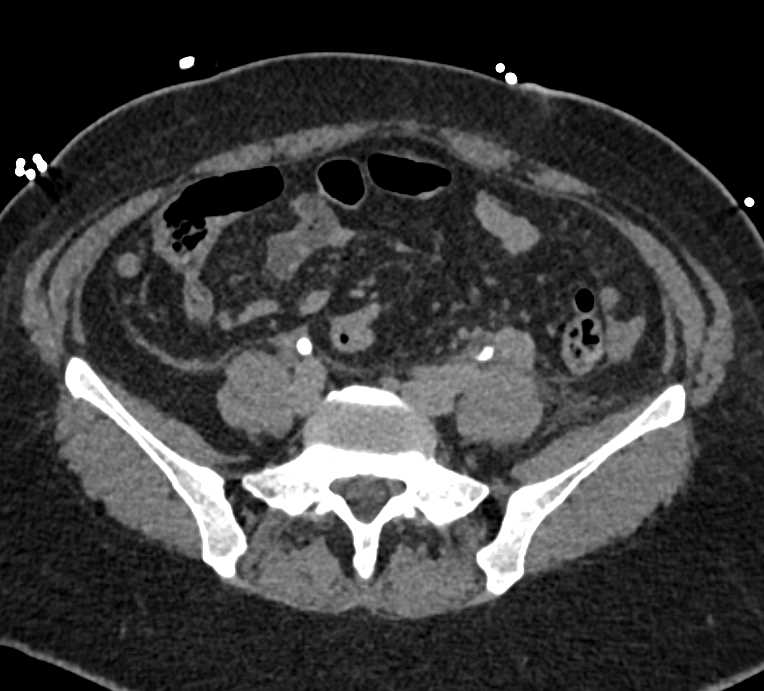

Acute Pyelonephritis Right Kidney